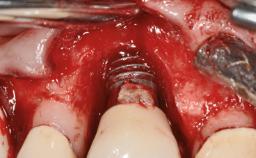

A 77-year-old male patient was referred for the management of frequent and repeated acrylic fracture of his existing mandibular fixed full-arch implant-supported metal/acrylic prosthesis. He also complained about softtissue soreness and the lack of retention and stability of his maxillary removable partial metal/acrylic prosthesis. Both prostheses had been delivered two years previously as part of his full-mouth rehabilitation (caries, tooth wear, tooth fracture). His medical history revealed high blood pressure, controlled with the use of antihypertensive medication.

# of Implants 5

Type of Implants Two-Piece